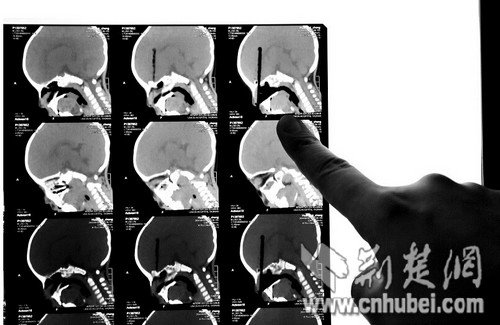

图为:CT扫描显示筷子插入颅内8厘米

当时接诊的是该院神经外科主治医师雷德强博士,他说:“当时成成神智尚清,四肢可以活动,但出现精神差、嗜睡、间歇性哭泣的反应,鼻腔还有血液流出。”经过3D的CT扫描,医生们发现,一次性筷子由鼻腔经过筛窦插入孩子颅内,颅内长度近8厘米,在鼻腔内大概有三四厘米,情况危急,需要立即手术。